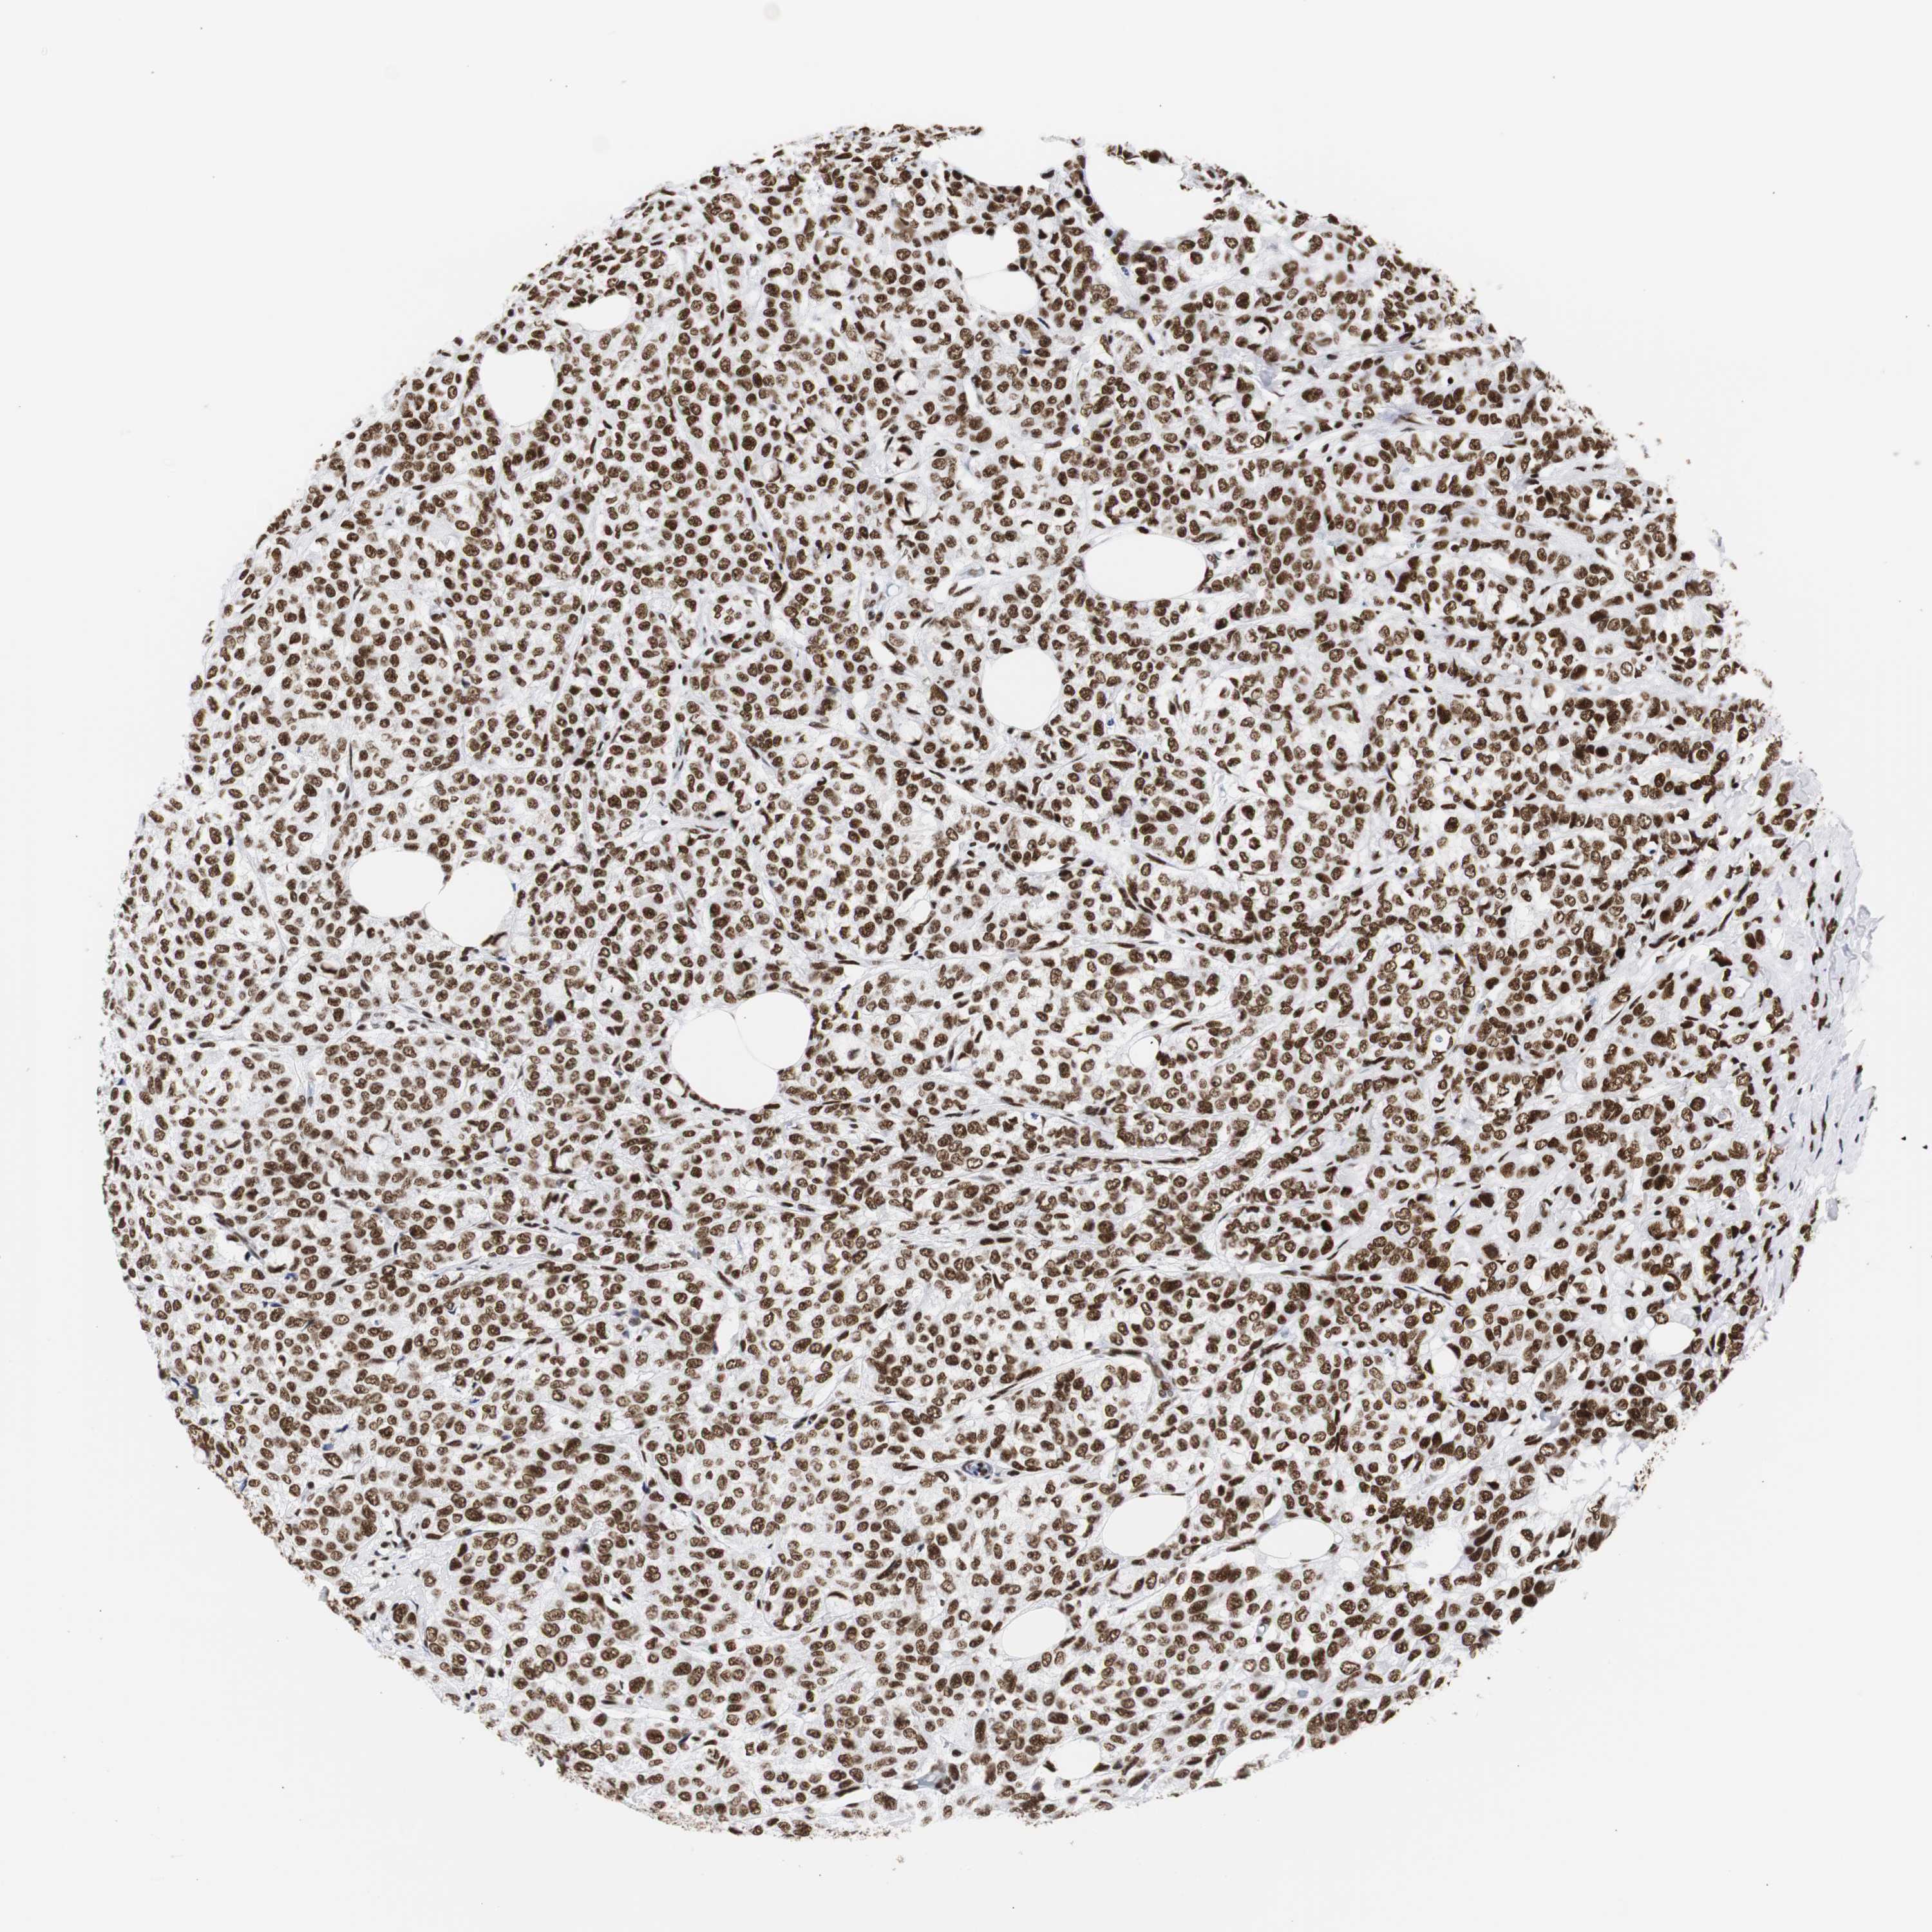

CANCER BREAST CANCER Show tissue menu

BRCA TCGA BRCA VALIDATION PROTEIN EXPRESSION